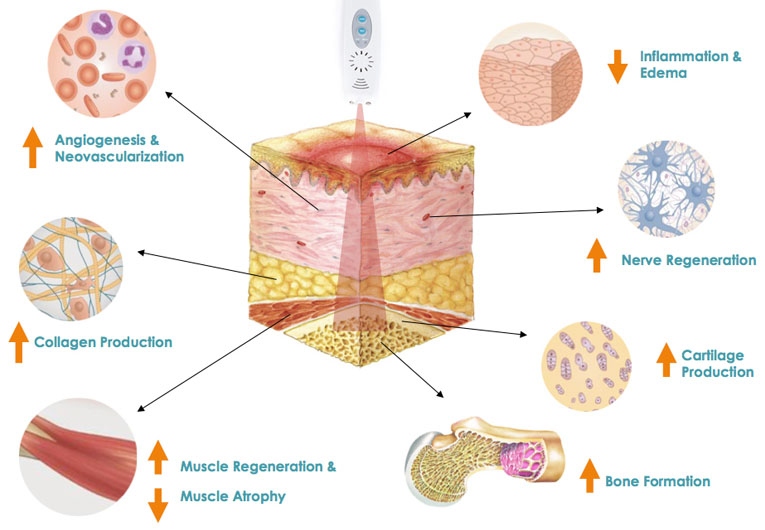

Application of Focused Ultrasound Waves stimulates connective tissue of mucous membrane to regenerate.

The apparatus therapeutic effect is based on thermal effects enabling focused ultrasound waves to precisely target tissue and the depth NOT impairing any structures through which they travel. Transformation of HIFU waves energies into thermal energies achieves therapeutic effects which are exclusively NON-ABLATIVE and BIOSTIMULATIVE enabling the treatment to stimulateneosynthesis of collagen and its regeneration and reorganisation. It also encourages neovascularization of the treated area.

In recent years HIFU technology has been successfully applied in treatments of vaginal relaxation (VRS) and stress incontinence (SUI). Precise application of HIFU waves to vaginal walls at a depth of 3 to 4.5mm warms submucosa and mucous membrane to 65⁰C. This method practically instigates connective tissue of mucous membrane to regenerate. The treatment results in higher numbers of stronger, remodeled and narrowed collagen fibers which permeate and provide strength of vaginal walls. In addition, biostimulative effects of HIFU wave initiated regenerative processes have positive impacts on the elastic fibers of mucosa and pelvic muscles. Final results of the treatment are reflected by a narrowed vaginal canal with stronger, more resistant and healthier walls. All these effects are beneficial in the treatment of SUI hence why HIFU is also applied in treatments of first and second degree SUI whilst third degree SUI requires surgery. HIFU application in treatment of first and second degree SUI can significantly delay the development of third degree SUI and therefore delay or completely eliminate the need for surgical treatment.